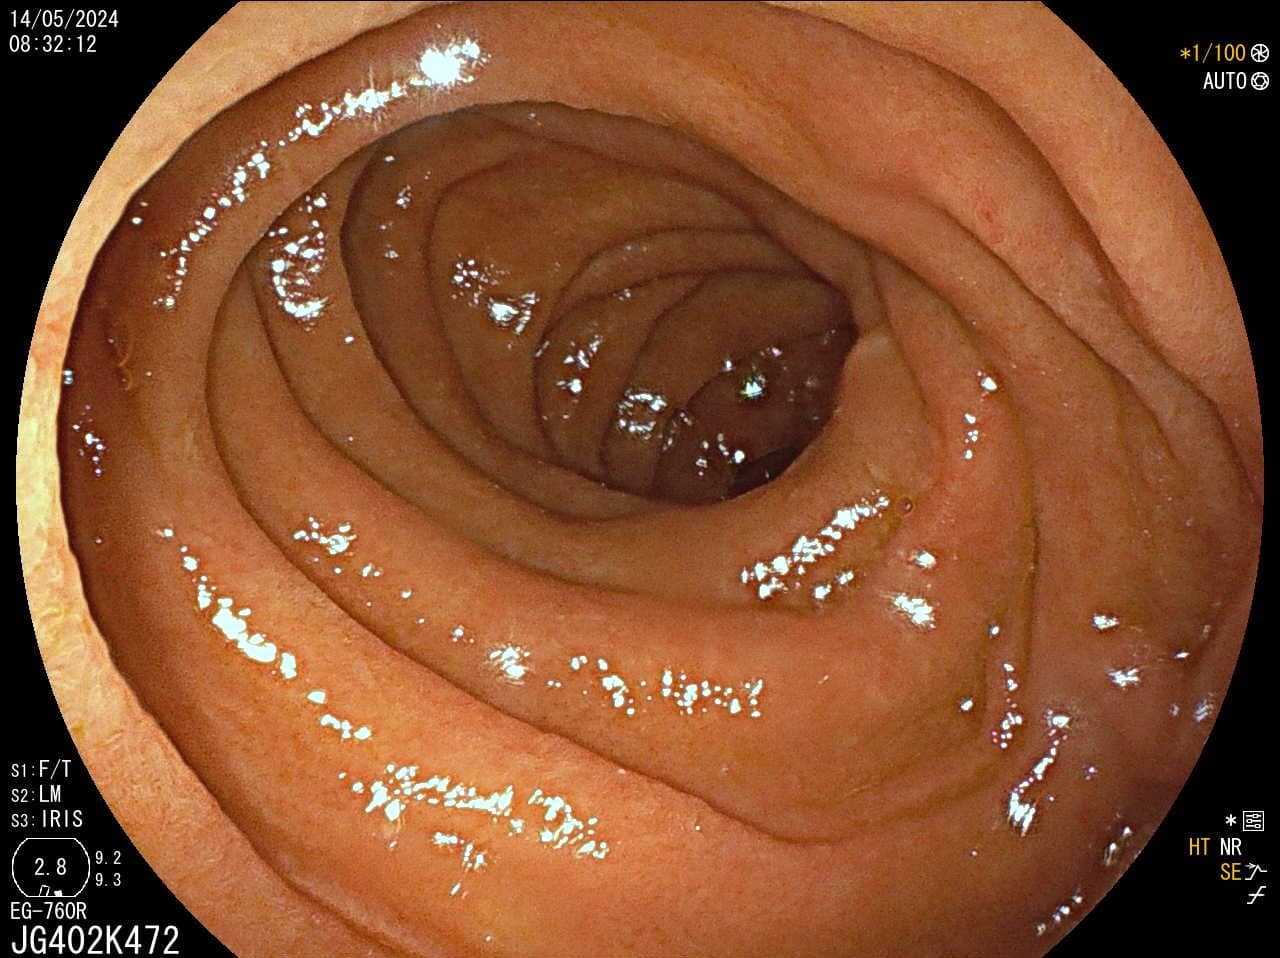

Pregled debelog crijeva

Kako bi pregled debelog crijeva bio temeljit potrebna je dobra priprema crijeva (očišćenost), no mali i plitki polipi, unatoč optimalnim uvjetima pretrage mogu ostati nezamijećeni, a zbog anatomije crijeva i skriveni iza nabora.